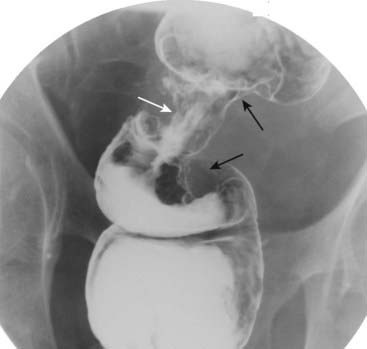

Figure 18-18 Intussusception, barium enema, and CT scan.

A, When one loop of bowel prolapses inside the loop immediately distal to it, the resultant obstruction produces a coiled-spring appearance on barium enema examination as two loops of bowel are superimposed on one another (solid white arrow). B, In another patient with an intussusception, a loop of large bowel (solid white arrow) is seen prolapsing into the loop distal to it (solid black arrow) producing a filling defect and obstructing the lumen.